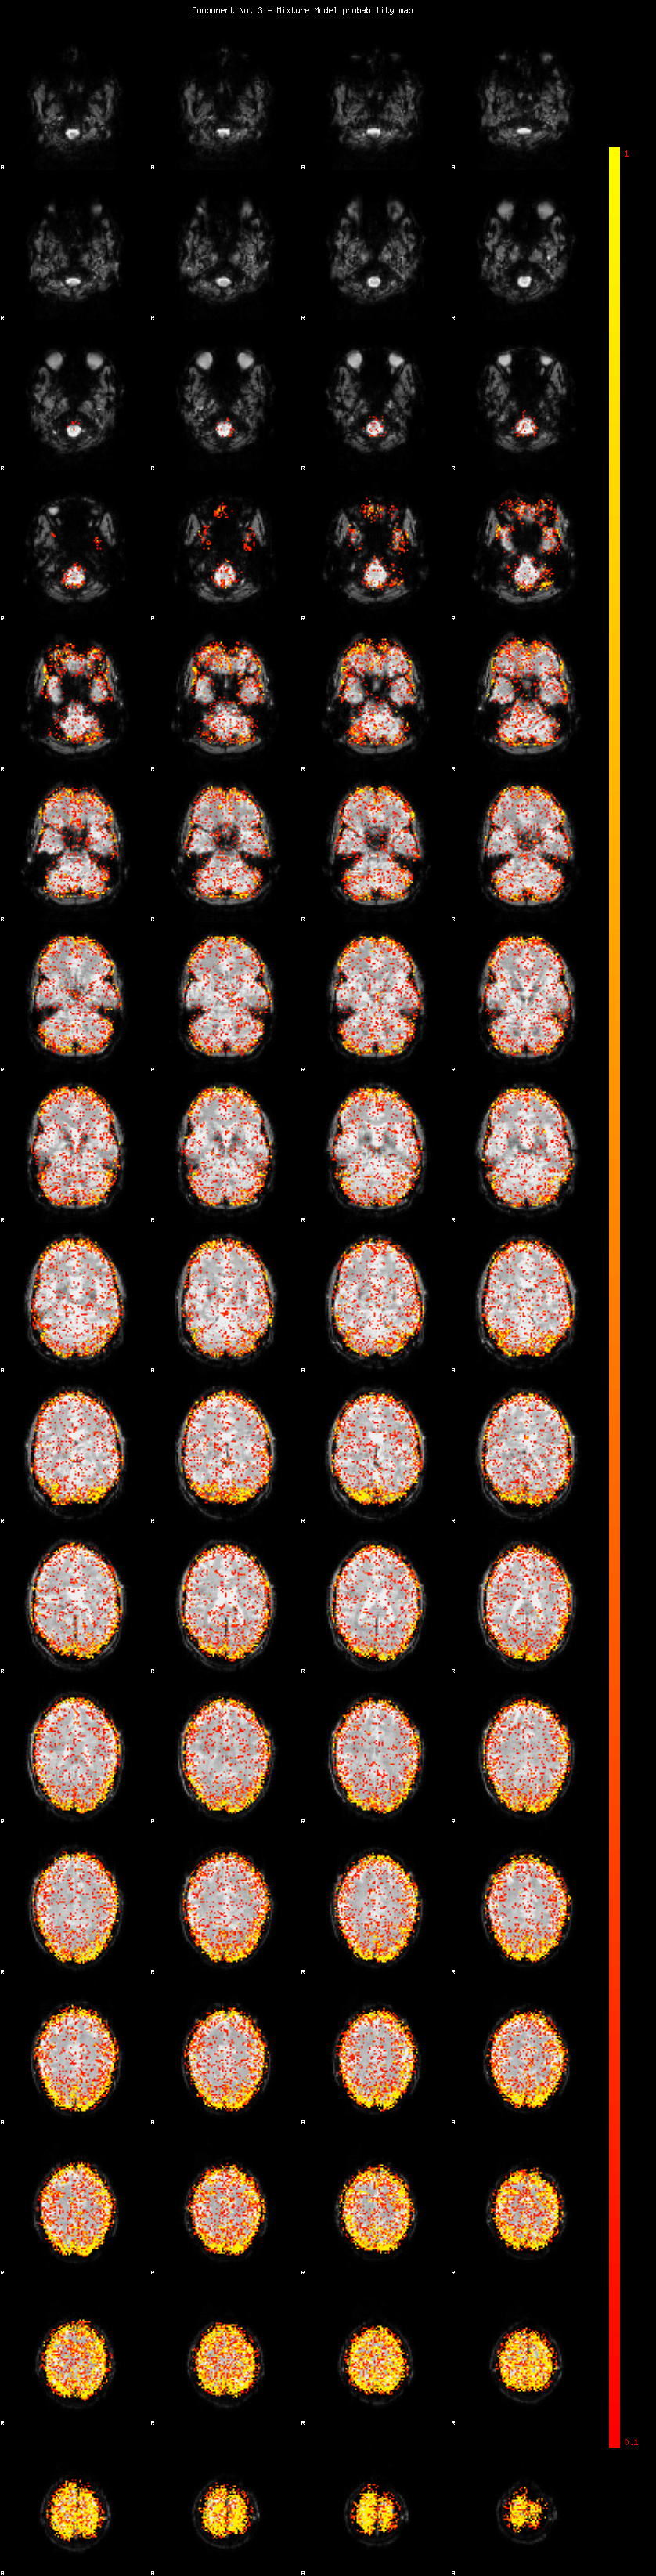

IC_3 Mixture Model fit

Means : -0.000000 3.743738 -2.864886

Vars : 1.000000 6.523501 3.312811

Prop. : 0.841294 0.088495 0.070211